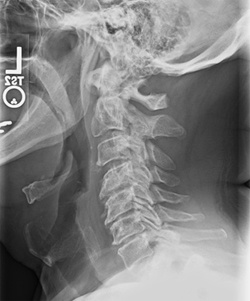

Phase Two Subluxation Degeneration

Phase Two is generally associated with subluxations that have existed for 20 to 40 years. Many characteristics from Phase One are still present, including abnormal curvature and altered motion. However, new changes begin to appear:

• Reduced range of motion

• Noticeable narrowing or flattening of disc spaces

• Calcium deposits or bone spurs forming around the affected joints

Although some patients may begin to feel stiff or achy, many still report few or no symptoms.

Chiropractic reconstructive care for Phase Two typically ranges from 1.5 to 2.5 years.

If left uncorrected, this degeneration progresses into the next phase.